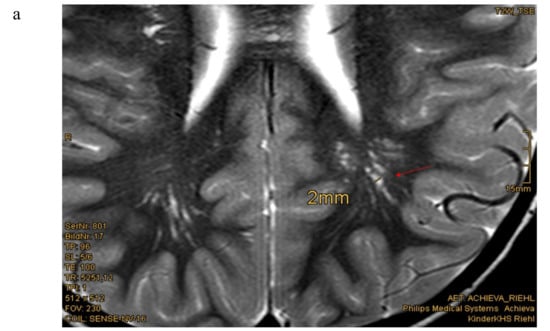

Eighteen of nineteen patients exhibited variations in cMRI. In 17 of 19 patients, we were able to re-analyze the MRI scans. In two cases, we only obtained medical reports, which were reported to be normal, even though enlarged perivascular spaces were described in one of these two patients. Medical reports of our patient cohort described enlarged perivascular spaces (EPVS), also known as Virchow–Robin Spaces (VRS), in six patients. However, when we re-analyzed the MRI pictures with special focus on EPVS, we found enlarged perivascular spaces in a total of eighteen patients (18/19). In some patients, these findings were quite evident (Figure 1b). Seven patients (7/17) presented with white matter abnormalities (Figure 2). Further pathologies included a cavernoma at the right side of the cerebellum, subependymal heterotopia at the top of the lateral cerebral ventricle, arachnoid cysts (in two), a Chiari malformation type I and a clinical diagnosis of pseudotumor cerebri with ventriculoperitoneal shunt in one patient (Table 1).

Figure 1.

Enlarged perivascular spaces (EPVS) in cerebral MRI (a) Patient 15: 4.5 year-old boy, T2w-image, EPVS 2 mm diameter [Courtesy Kinderkrankenhaus Kliniken der Stadt Köln]. (b) Patient 23: 12.5 year old girl, T2 weighted image, sagittal view, pronounced EPVS up to 3 mm diameter [Courtesy Dr. A. Wieschen, Institut für Radiologie und Nuklearmedizin, GPR Klinikum Rüsselsheim].